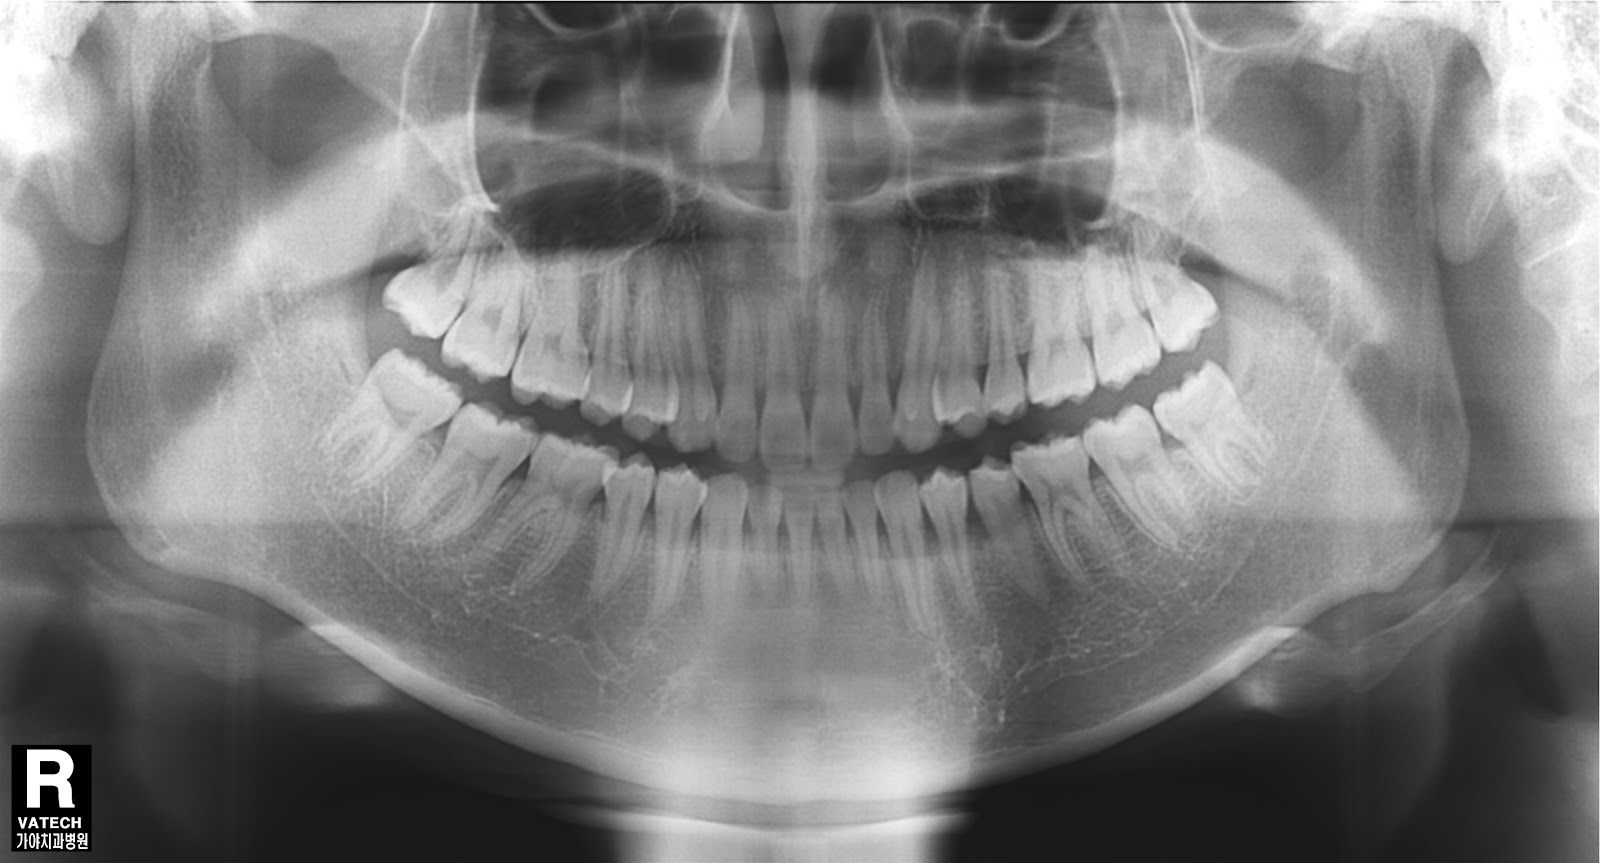

What Is Image Density In Radiography . The overall blackness of the image is referred to as the radiographic density or optical density (od). A radiography image appears in different shades of gray, like white black, greyish, or patchy or bright white somewhere. A radiograph must have sufficient density to visualize the anatomic. The contrast of an image gets produced by the difference in tissue density displayed on a radiograph, and it can thus be manipulated to distinguish an area of interest. When the radiographic density is optimum, the image is both dark enough. Radiographic density (aka optical, photographic, or film density) is a measure of the degree of film darkening. The amount of darkness in the radiographic image reflects the radiographic density. Very dense material such as. Radiographic density is the amount of overall blackness produced on the processed image. It is called transmitted density in conventional film. Low density material such as air is represented as black on the final radiograph. Technically it should be called. The radiographic density is defined as the level of darkness in an x ray image, calculated by the radiation absorption by those tissues in that radiographic image.